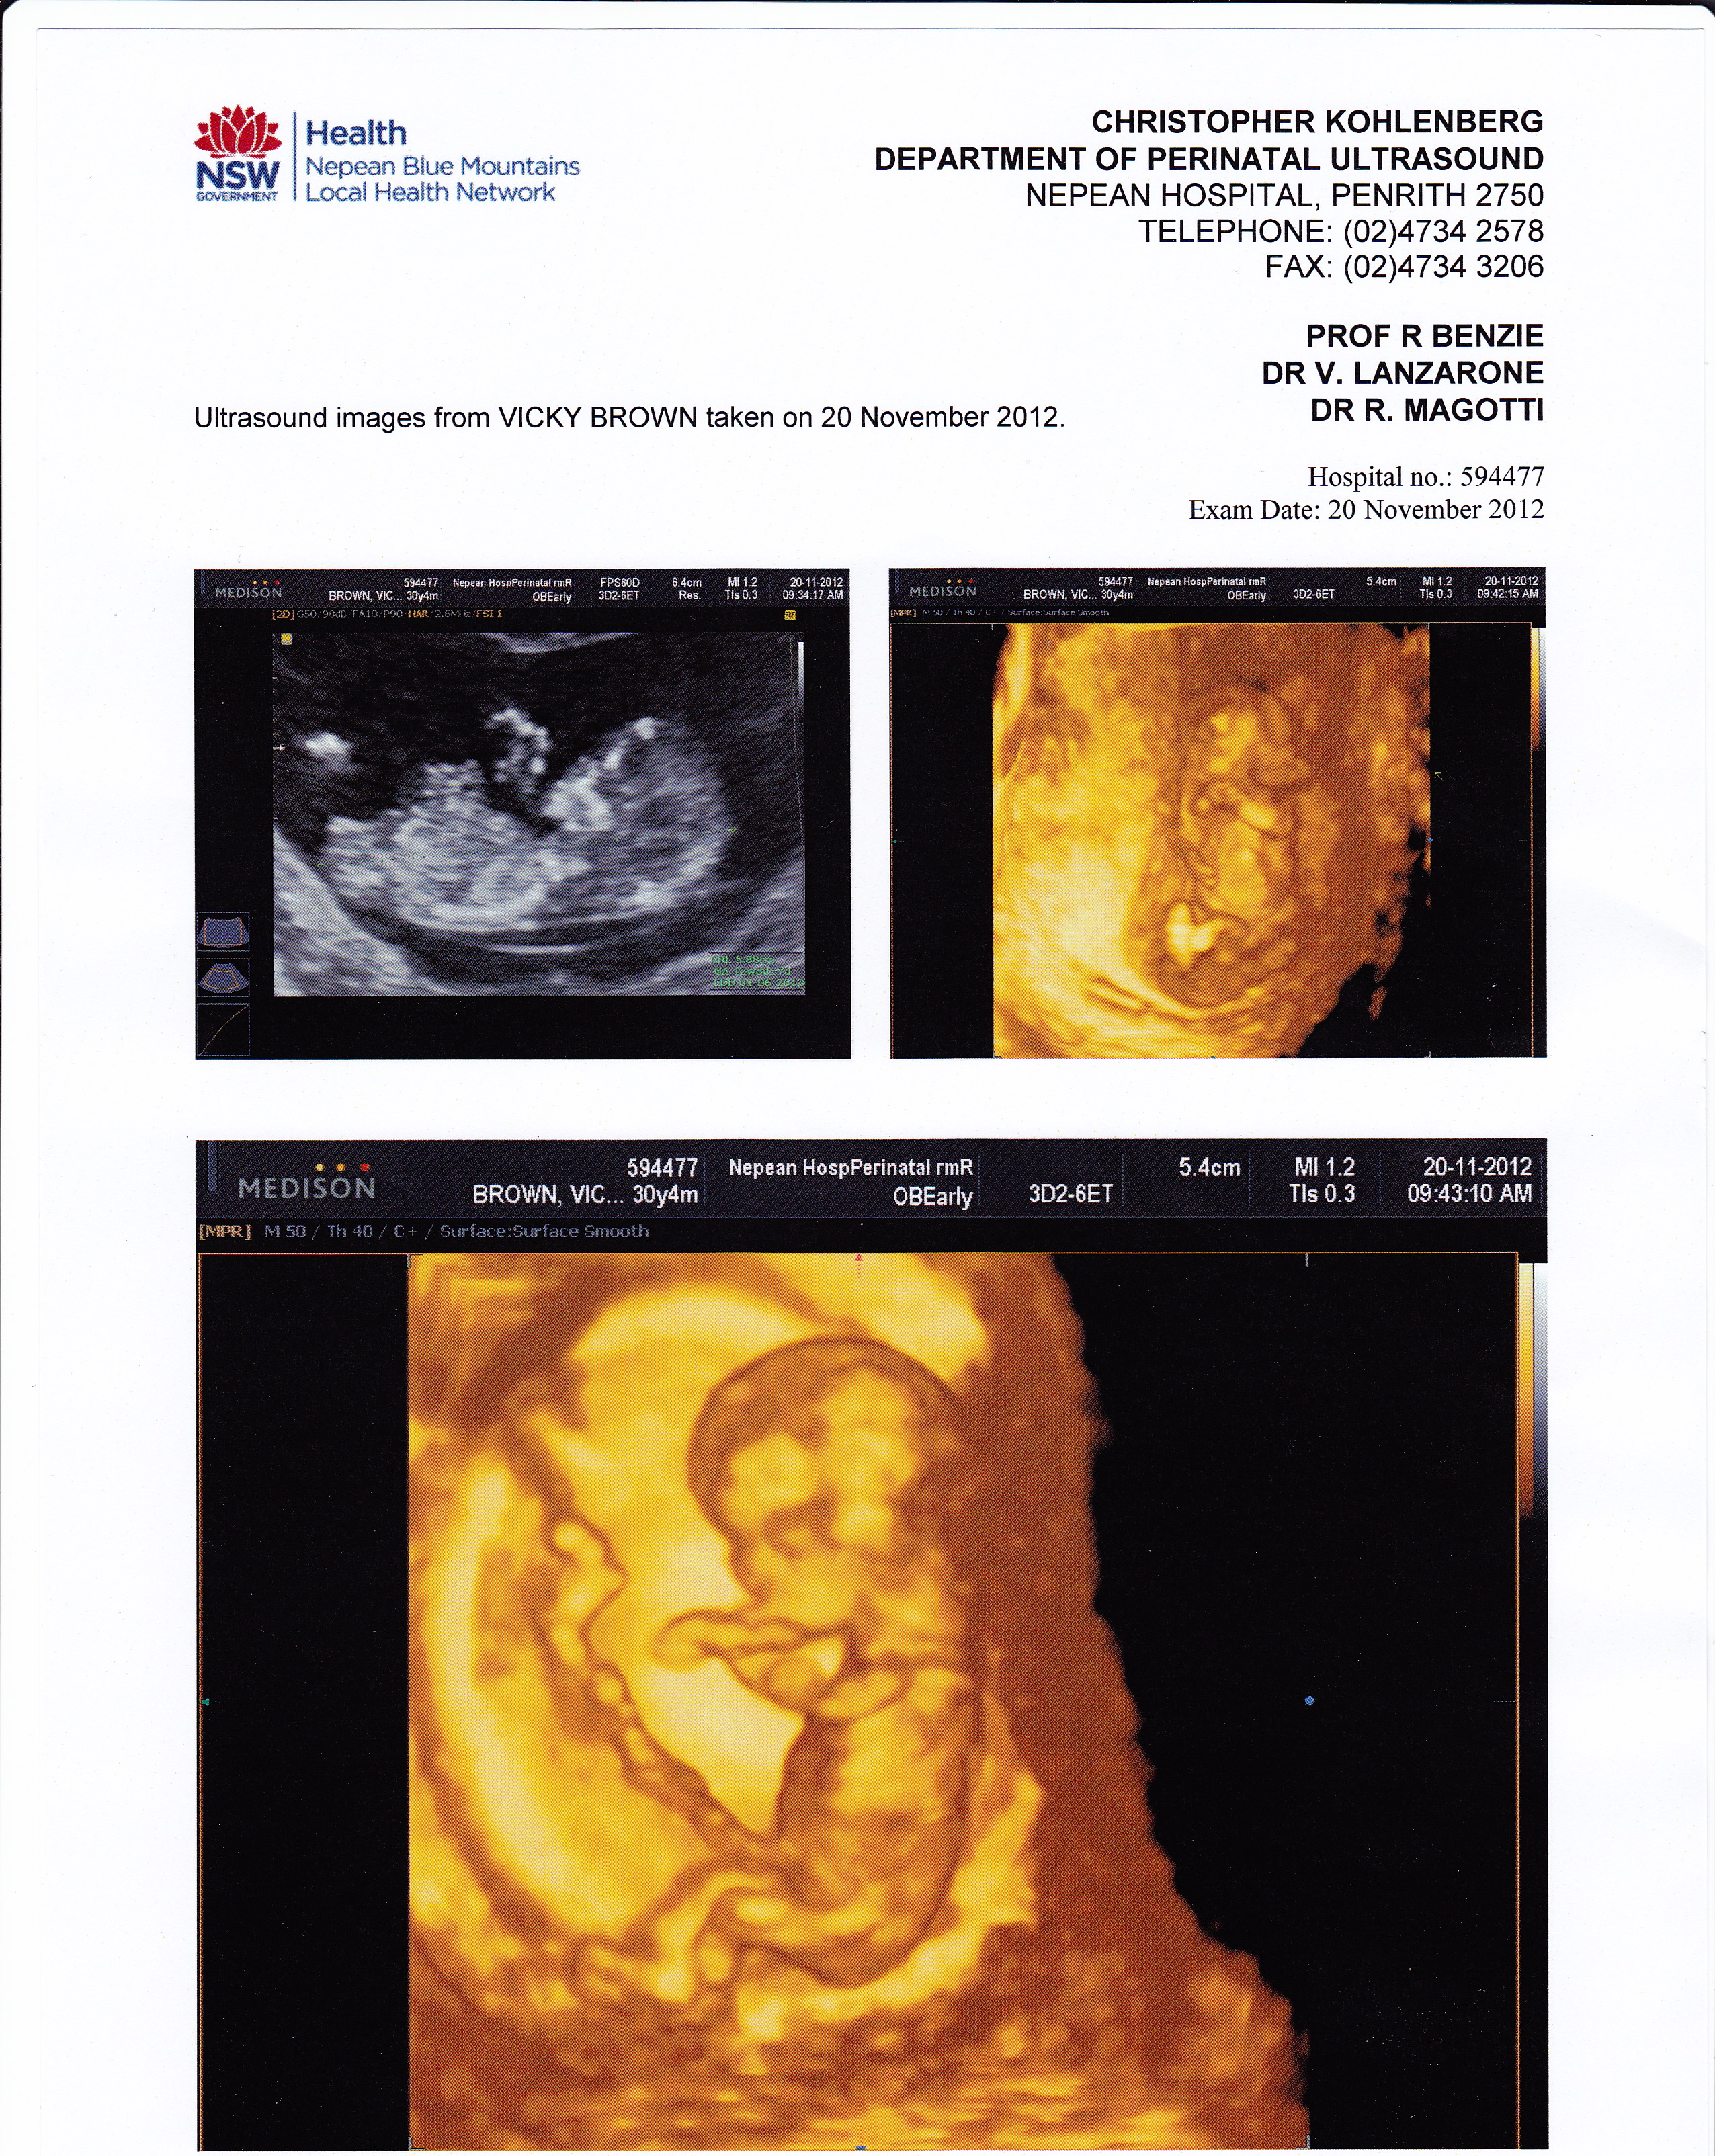

I am also leaning boy. The nub is flattish but the angle is upward. Also, the b/w pic has a boyish skull and nub.

Thanks everyone - do u know how accurate skull theory is? so many theories out there. I know this baby is attached to left side which ties in with another theory, nub theory has guessed 50 girls against 4 boy comments with 3 ultrasound techs guessing girl . I took urine test and came back girl. this is going to be an interesting outcome in 17 days :) as I will post results...

I would guess girl based on nub, it look parallel to the spine. Side of implantation though (unless checked at an early gestation) does not reflect gender at this stage. Did you sway or have a preference?